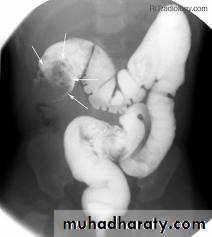

Intussusceptions'

Intussusceptions' occurs when one segment of bowel is pulled into itself (or a neighboring loop of bowel) by peristalsis.It is an important cause of an acute abdomen in children and merits timely ultrasound examination and reduction to preclude significant sequelae including bowel necrosis.

Intussusception may also occur in the adult population where it is usually caused by a focal lesion acting as a lead point.

Abdominal plain film

Abdominal x-rays may demonstrate an elongated soft tissue mass (typically in the right upper quadrant in children) with a bowel obstruction proximal to it.

Fluoroscopy - contrast enema

A contrast enema remains the gold standard, demonstrating the intussusceptions as an occluding mass prolapsing into the lumen, giving the "coiled spring” appearance .